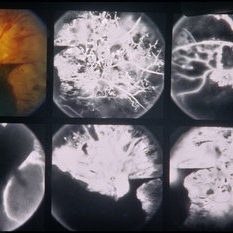

PDR

Jan 24 2014 by Howard Schatz, MD

63-year-old female. Right eye 20/25 and left eye 20/125.